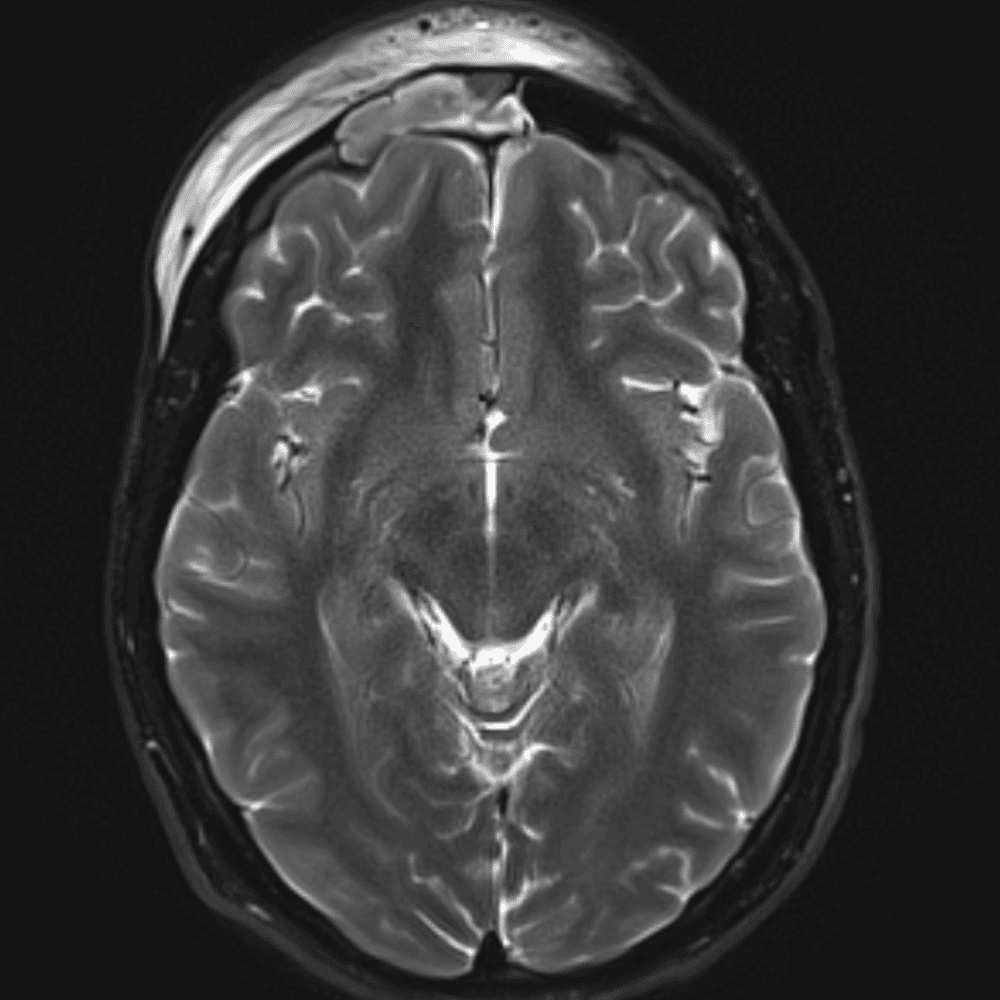

๋‹น์ง ์‹œ ํ”ํžˆ ๋ณผ ์ˆ˜ ์žˆ๋Š” ์‚ฌ๋ก€์˜ ์ „ํ˜•์ ์ธ ์˜ˆ๋ฅผ ํฌํ•จํ•ฉ๋‹ˆ๋‹ค.

39 ์‚ฌ๋ก€

์—ฐ์Šต

๋ฏธ๋ฌ˜ํ•˜๊ฑฐ๋‚˜ ์–ด๋ ค์šด ์‚ฌ๋ก€์™€ ์ผ๋ถ€ ์ •์ƒ ์‚ฌ๋ก€๋ฅผ ํฌํ•จํ•˜์—ฌ ๋‹น์ง์„ ์‹œ๋ฎฌ๋ ˆ์ด์…˜ํ•ฉ๋‹ˆ๋‹ค.

50 ์‚ฌ๋ก€